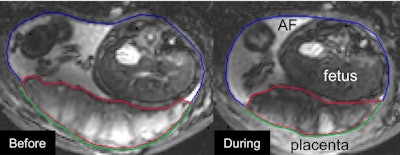

However, what truly surprised the authors was a placental-uterine contraction that occurred during a 10-minute timespan for 19 of the women in the study, including 35% of women with normal pregnancies and 70% with preeclampsia.

The so-called utero-placental pump reduced the area and thickness of the myometrium that underlies the placenta. It also stretched the rest of the uterine wall and reduced placental volume by up to 40%.